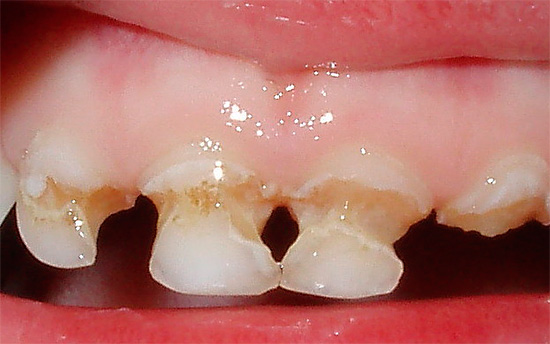

Em maior medida, a cárie circular afeta os dentes de leite, especialmente em crianças enfraquecidas.Também é chamado de "anular" ou "anular".

Na foto abaixo, você pode ver um exemplo de cárie circular nos dentes do bebê:

É fácil adivinhar que a cárie circular, por ser mais agressiva, geralmente ocorre com sintomas clínicos graves e, às vezes, leva a fraturas ou lascas da coroa do dente afetado. No entanto, em alguns casos, mesmo esses defeitos graves podem não causar dor intensa, pois produzem dentina de reposição que protege a polpa da irritação.